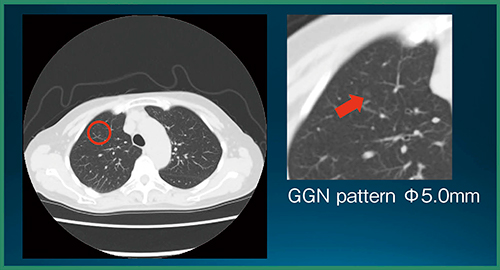

読影実験の結果,CADe単体の検出率は89.2%(66/74結節),未検出数は0.27個/症例,結節以外の誤検出数は0.73個/症例であった。また,統計解析の結果,評価者全員の平均FOM(figure of merit)は,CADeあり読影で有意に向上した(p=0.0009)(図3)。図4は,評価者は指摘せず,CADeが指摘した症例である。非常に淡いすりガラス状陰影であるが,背景肺に問題がなければCADeでの検出が可能である。また,図5は,評価者もCADeも指摘しなかった症例で,ごく淡い結節は検出が難しかった。

図5 評価者もCADeも指摘しなかった症例